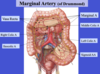

Label all:

Label: